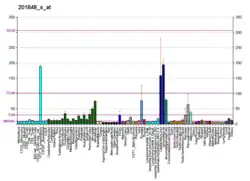

BNIP3 interacts with the E1B 19 kDa protein which is responsible for the protection of virally induced cell death, as well as E1B 19 kDa-like sequences of BCL2, also an apoptotic protector. This gene contains a BH3 domain and a transmembrane domain, which have been associated with pro-apoptotic function. The dimeric mitochondrial protein encoded by this gene is known to induce apoptosis, even in the presence of BCL2.[9] Change of BNIP3 expression along other members of the Bcl-2 family measured by qPCR captures important characteristics of malignant transformation, and are defined as markers of resistance toward cell death, a key hallmark of cancer.[10]